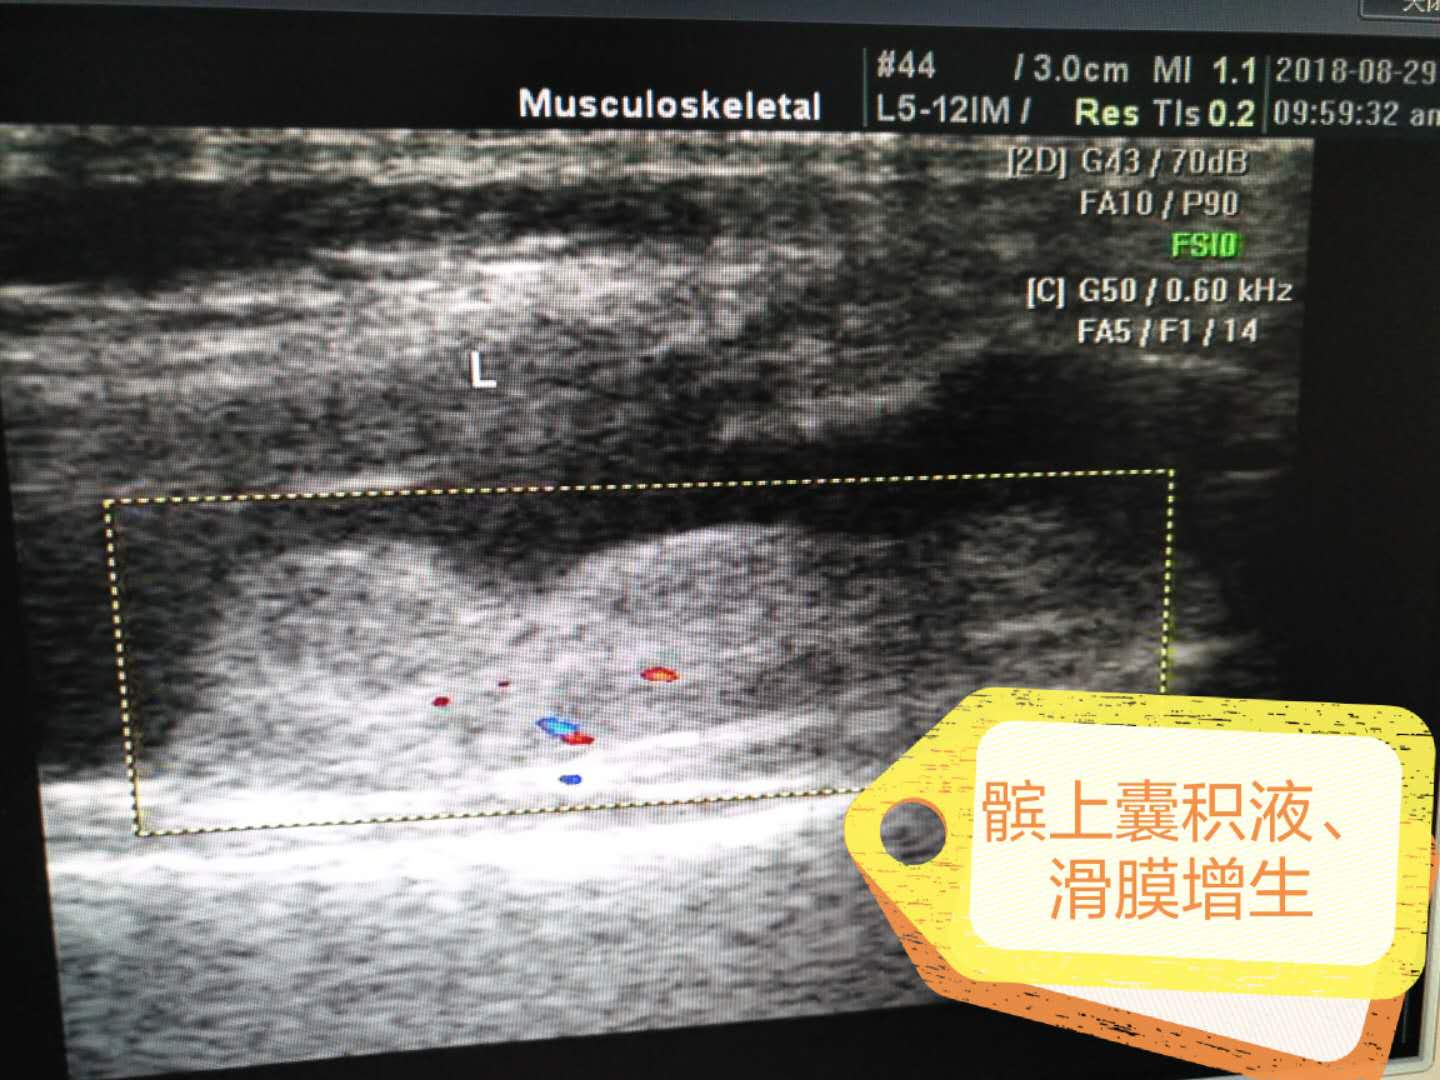

髕上囊積液、滑膜增生